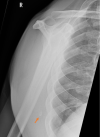

Inferior scapula avulsion fractures are rare injuries, with few cases reported and only a small number managed operatively discussed in the literature. We report the case of a man in his 40s who fell from a height and presented with right-sided scapular winging and point tenderness at the inferior pole of his right scapula with no neurological deficit. Radiographs and CT diagnosed avulsion fracture of the inferior scapula. The patient underwent surgical fixation and, following a course of physiotherapy, successfully recovered with no residual winging and full range of movement.